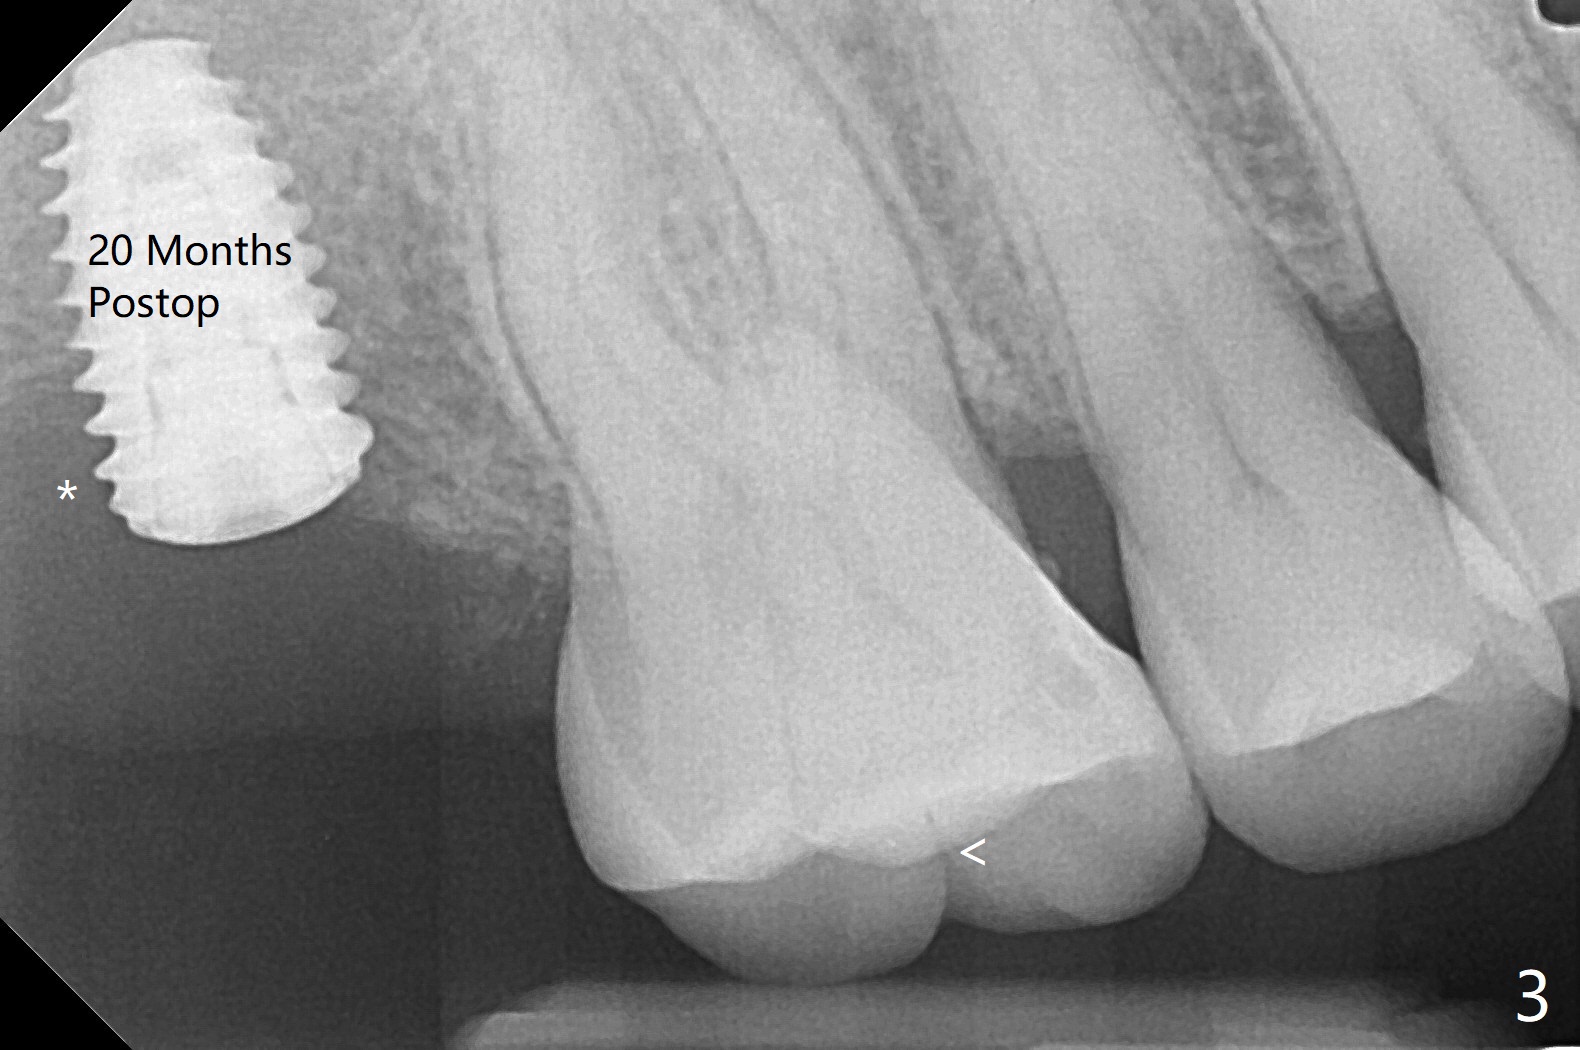

57岁男咬合力大,在右上7植体愈合中,6(3号牙)出现隐裂(图三),*:右上7植体远中缺骨。Uncover时植骨。